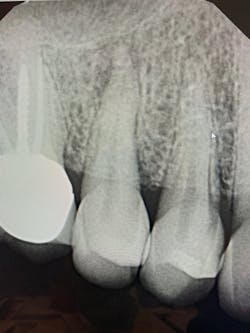

During the past 10 years, I’ve flown all over the US to mentor others in the placement of implants. The recommended compensation to the mentor is between $10,000 and $20,000 per day, funded through patient fees. Generally, the mentee nets more than $10,000 for the day as opposed to paying $10,000 to fly elsewhere for the teaching. These mentorship days are usually scheduled through an implant institute. If you are interested in being a mentor or being mentored, InstituteFaculty.com offers a detailed video explanation. The various clinical cases and figures in this article demonstrate the typical cases that would be included in a standard over-the-shoulder mentorship day. (See figures 1–6.)

![Figure 2: Self-tapping implant placed sub-crestal to maximize esthetics with a morse taper connection (MorsTorq [iH Biomedical]) Figure 2: Self-tapping implant placed sub-crestal to maximize esthetics with a morse taper connection (MorsTorq [iH Biomedical])](https://img.dentaleconomics.com/files/base/ebm/de/image/2019/09/1908DECfra_p02.5d7939647f8bf.png?auto=format,compress&fit=max&q=45?w=250&width=250)

![Figure 4: Immediate placement of implant with sharp, osseo-compatible threads allowing for a high degree of primary stability (MorsTorq [iH Biomedical]) Figure 4: Immediate placement of implant with sharp, osseo-compatible threads allowing for a high degree of primary stability (MorsTorq [iH Biomedical])](https://img.dentaleconomics.com/files/base/ebm/de/image/2019/09/1908DECfra_p04.5d7939647074c.png?auto=format,compress&fit=max&q=45?w=250&width=250)

![Figure 6: Immediate implant with aggressive, osseo-condensing threading used with a high torque value and primary stability (iHex1 [iH Biomedical]) Figure 6: Immediate implant with aggressive, osseo-condensing threading used with a high torque value and primary stability (iHex1 [iH Biomedical])](https://img.dentaleconomics.com/files/base/ebm/de/image/2019/09/1908DECfra_p06.5d793ec3138fa.png?auto=format,compress&fit=max&q=45?w=250&width=250)